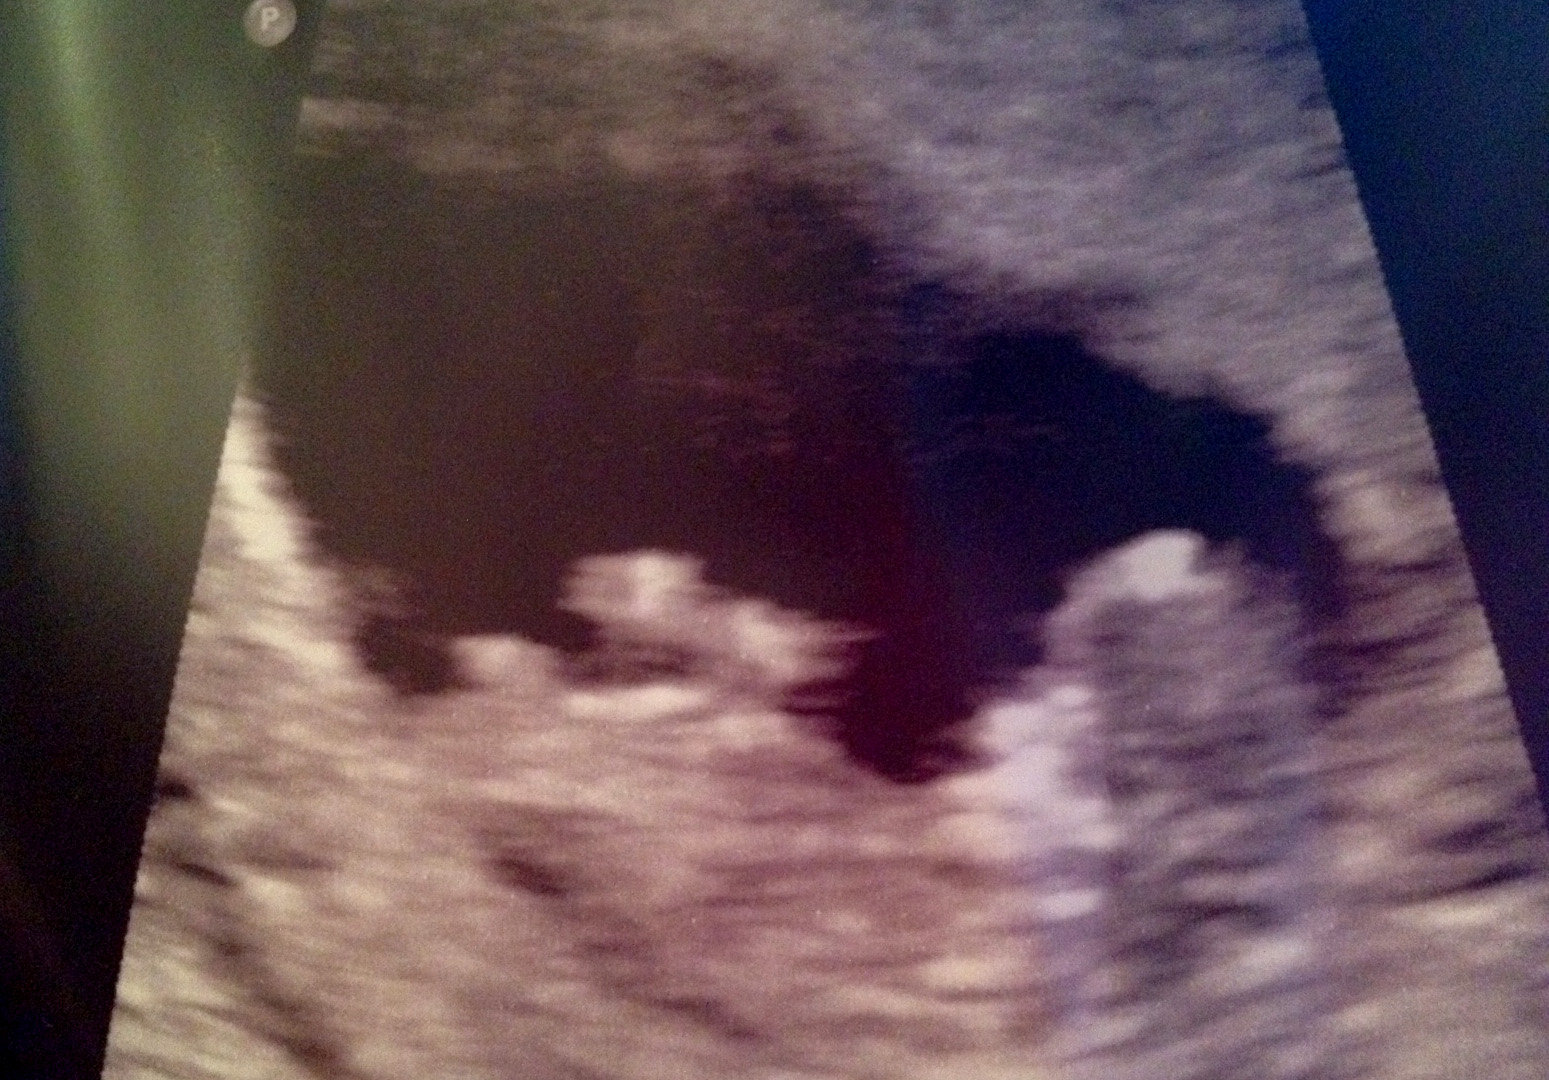

Hi, I am brand new to the site! This was my ultrasound scan from my 12 week...I don't think I see a nub but any guesses on skull? Thank you all so much!!! :)Attachment 4226

maybe boy by skull

Going boy

Strange view I have no clue!